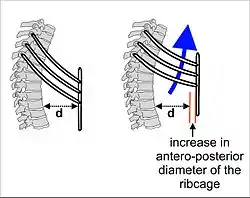

Expansion of the thoracic cavity is driven in three planes; the vertical, the anteroposterior and the transverse. The vertical plane is extended by the help of the diaphragm contracting and the abdominal muscles relaxing to accommodate the downward pressure that is supplied to the abdominal viscera by the diaphragm contracting. A greater extension can be achieved by the diaphragm itself moving down, rather than simply the domes flattening. The second plane is the anteroposterior and this is expanded by a movement known as the 'pump handle'. The downward sloping nature of the upper ribs are as such because they enable this to occur. When the external intercostal muscles contract and lift the ribs, the upper ribs are able also to push the sternum up and out. This movement increases the anteroposterior diameter of the thoracic cavity, and hence aids breathing further. The third, transverse, plane is primarily expanded by the lower ribs (some say it is the 7th to 10th ribs in particular), with the diaphragm's central tendon acting as a fixed point. When the diaphragm contracts, the ribs are able to evert (meaning turn outwards or inside out) and produce what is known as the bucket handle movement, facilitated by gliding at the costovertebral joints. In this way, the transverse diameter is expanded and the lungs can fill.

The circumference of the normal adult human rib cage expands by 3 to 5 cm during inhalation.[15]